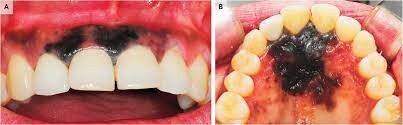

Oral Cancer

In rare cases, benign lesions that don't require treatment may transform into oral malignant melanoma, a type of oral cancer. A doctor will look at a range of factors to see if the lesion qualifies as melanoma. According to a research article published in the Journal of Indian Academy of Oral Medicine and Radiology, melanoma constitutes only 3–5% of all cutaneous malignancies, and oral melanoma is an aggressive neoplasm which accounts for less than 0.5%.

If you believe you have oral cancer symptoms, we recommend leaving the diagnosis up to the professionals and speaking to your doctor. If you exhibit symptoms, they may perform a biopsy (laboratory tests of your tissue) to confirm melanoma.